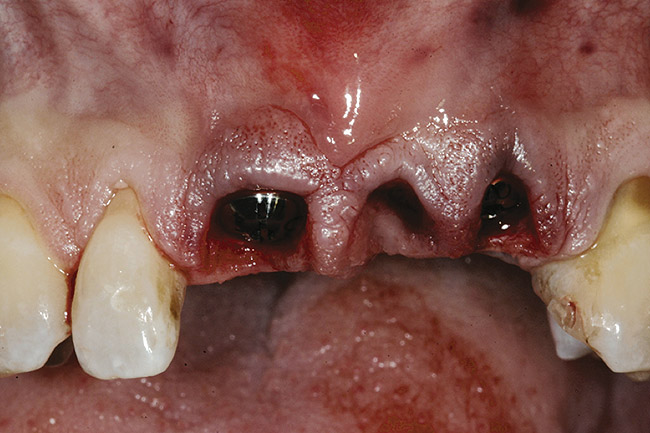

Figure 25  A patient presented with a significant ridge defect, but with surgeon-placed adjacent implants in the lateral and cuspid positions.

Figure 25

Figure 26  A pediculated connective-tissue graft was used to augment the soft-tissue height.

Figure 26

Figure 27  The lateral incisor implant was put to sleep and the cuspid implant uncovered.

Figure 27

Figure 28  The final restoration exhibits a cantilevered incisor off of a canine implant.

Figure 28